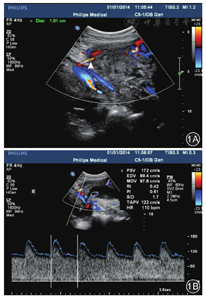

子宫动脉:均选择右侧子宫动脉。先从子宫下段肌层与右侧盆壁间找到右侧髂内动脉,再从其远端分支与髂内动脉呈十字交叉通过髂外动脉1 cm处获取子宫动脉频谱图(图1A),应用脉冲多普勒技术测量相应血流动力学参数值(图1B)。